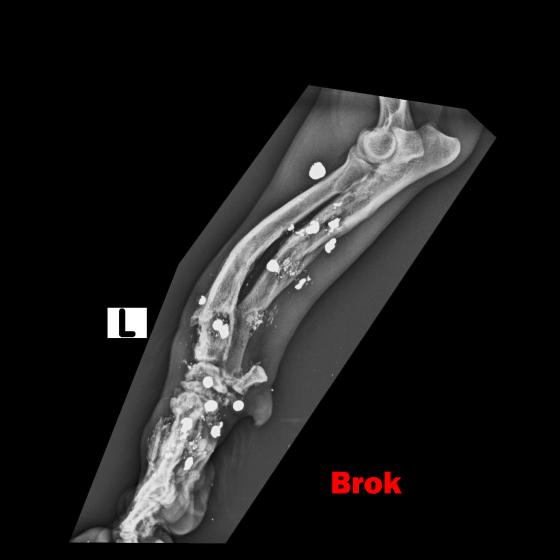

BROK - dostal meno Brok, keďže sa stal živým terčom a má vo svojom malom telíčku nespočetné množstvo brokov. Labka je vykrivená preto, že sa mu v dôsledku streľby dolámali kosti...

Image removed.BROK - dostal meno Brok, keďže sa stal živým terčom a má vo svojom malom telíčku nespočetné množstvo brokov. Jeho brata sme odchytili pár mesiacov pred ním, keď do neho deti hádzali petardy. On z toho vyviazol bez problémov, ale žiaľ Brok to šťastie už nemal. Jeho celá nožička je zdeformovaná, dostieľaná, dolámaná. On nenatrafil na deti, ale na dospelého, zjavne psychicky narušeného človeka, ktorý mu neskutočne ublížil. Odpusťte mi, keď do prosby vnesiem aj emócie, ale pri pohľade na neho sa topím v slzách. Brok je jeden z najláskavejších psíkov akého sme kedy mali. Miluje ľudí, objíma ich aj tou boľavou nožičkou. Rozdáva pusinky každému. Má celý život pred sebou. Tak rád by bezstarostne behal a naháňal sa, ale potkne sa aj o vlastnú nohu. Skáče na človeka, akoby sa odprosoval, že už nikdy viac nebude neposlušný, len nech mu už nikto neublíži. Chce dokázať, že je dobrý, že nadovšetko miluje a nechce ho pustiť, už nikdy viac nechce byť bez svojho človeka. Toľko toho ešte môže a musí zažiť! Potrebuje svoju nožičku a musíme mu pomôcť. Bude to nákladné, ale toto je jednoducho situácia, ktorú musíme vyriešiť a dopriať mu plnohodnotný život. Brok má v nešťastí obrovské šťastie. Keď sme si mysleli, že jediným riešením bude amputácia, ujal sa ho najlepší ortopéd v republike, MVDr. Vatolík a nožičku mu vie napraviť. Bročko ale potrebuje Vašu pomoc, lebo bez nej to nepôjde. Diagnostiku a prvú operáciu, odstránenie brokov z tkaniva má už úspešne za sebou. Zatiaľ má "len" malé ranky, z ktorých sa rýchlo zotaví. Momentálne čakáme na výsledky kultivácie. Tkanivo musí byť "čisté" bez akejkoľvek infekcie, bez akýchkoľvek baktérií, aby sa mohlo ďalej pokračovať.

Labka je vykrivená preto, že sa mu v dôsledku streľby dolámali kosti a keď sme ho našli, už bolo všetko zahojené a zle zrastené. Za diagnostiku a prvý zákrok máme faktúru vo výške 449,23€.

Ďalšia operácia, ktorá ho čaká 21.5.2020 bude ale veľmi náročná. Treba odstrániť broky z kostí, a tým pádom bude treba vyrezať časť zlomených a zle zahojených kostí v nožičke. Tieto časti sa následne nahradia implantátmi (pán doktor ešte zvažuje či použiť implantáty z titánu, ktoré sú prijateľnejšie pre organizmus, alebo implantáty z chirurgickej ocele, ktorá je pevnejšia). Bročko bude mať v nožičke vnútorné fixátory, ktoré ju budú držať pokope, kým sa opäť nezocelí. Nebude to žiadna prechádzka ružovou záhradou, ale zvládneme to! Z našej strany pre neho urobíme všetko a doprajeme mu plnohodnotný a bezstarostný štart do nového života. Potrebujeme ale Vašu pomoc. Náklady na operáciu sa predpokladajú do výšky okolo 1500€. Celkom teda za Bročka cca 2000€.